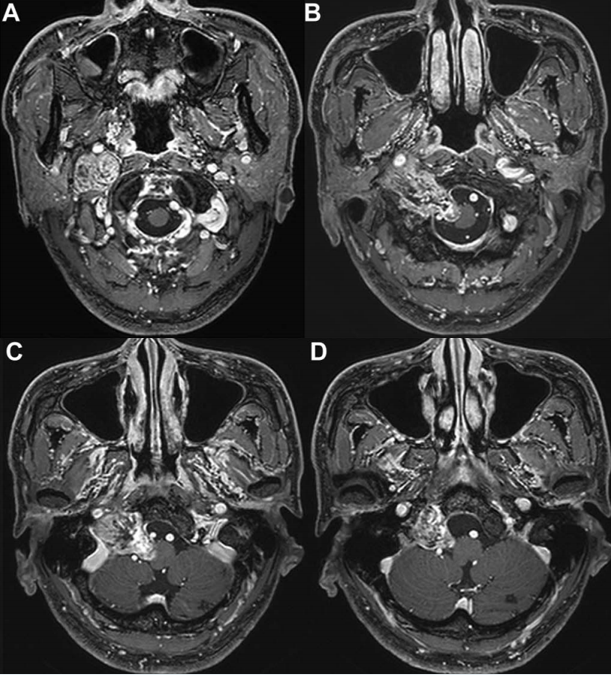

室管膜瘤是一种罕见的颅内肿瘤,约占所有颅内肿瘤的2%。其常见发生部位为后颅窝,这是儿童室管膜瘤的典型发病部位,但在成人和老年患者中亦有报道。由于后颅窝室管膜瘤常与第四脑室底...